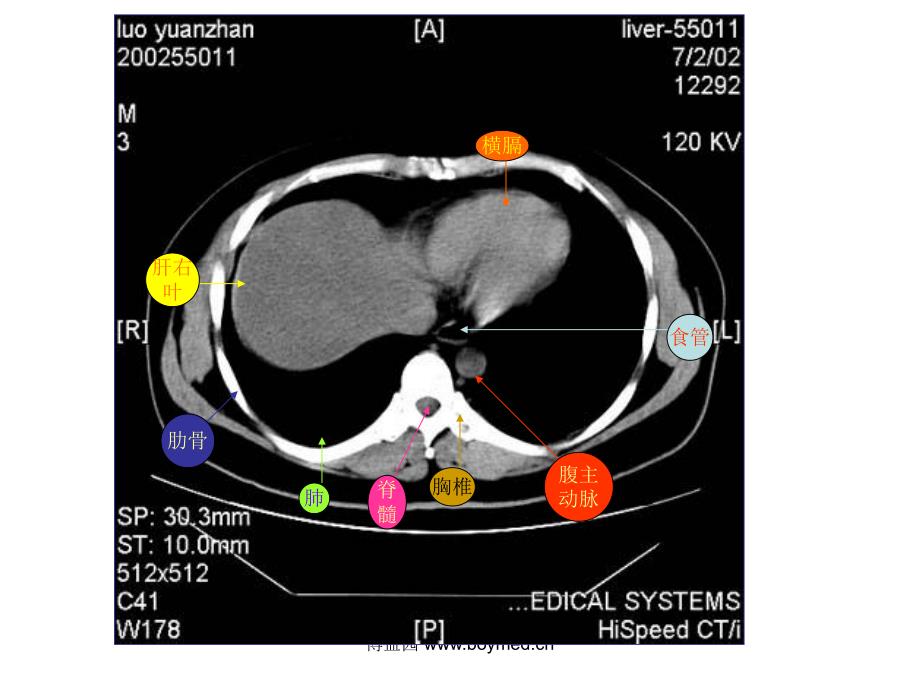

1、博益园 肝右叶横膈肺胸椎脊髓腹主动脉食管肋骨博益园 肋骨肝右叶腹主动脉食管肺博益园 肝左叶肝右叶腹主动脉胃脾肝尾叶博益园 肝右叶尾叶膈脚脾门静脉肝左叶胃博益园 肝右叶膈脚腹主动脉脾胆囊胃博益园 肝右叶下腔静脉胰腺脾胃腹主动脉博益园 肝右叶心脏腹主动脉下腔静脉脊髓食管肺博益园 肝左叶肝右叶腹主动脉下腔静脉胃脾脊髓博益园 肝左叶及肝左动脉肝右叶及肝右动脉腹主动脉下腔静脉胃脾肝尾叶博益园 肝右叶下腔静脉腹主动脉胃脾膈脚博益园 肝静脉下腔静脉腹主动脉食道肝右叶博益园 下腔静脉肝右叶肝静脉肝左叶腹主动脉胃脾肝尾叶博益园 肝右叶下腔静脉腹主动脉门静脉主干肝左叶胃脾博益园 肝右叶下腔静脉门静脉腹主动脉膈脚脾